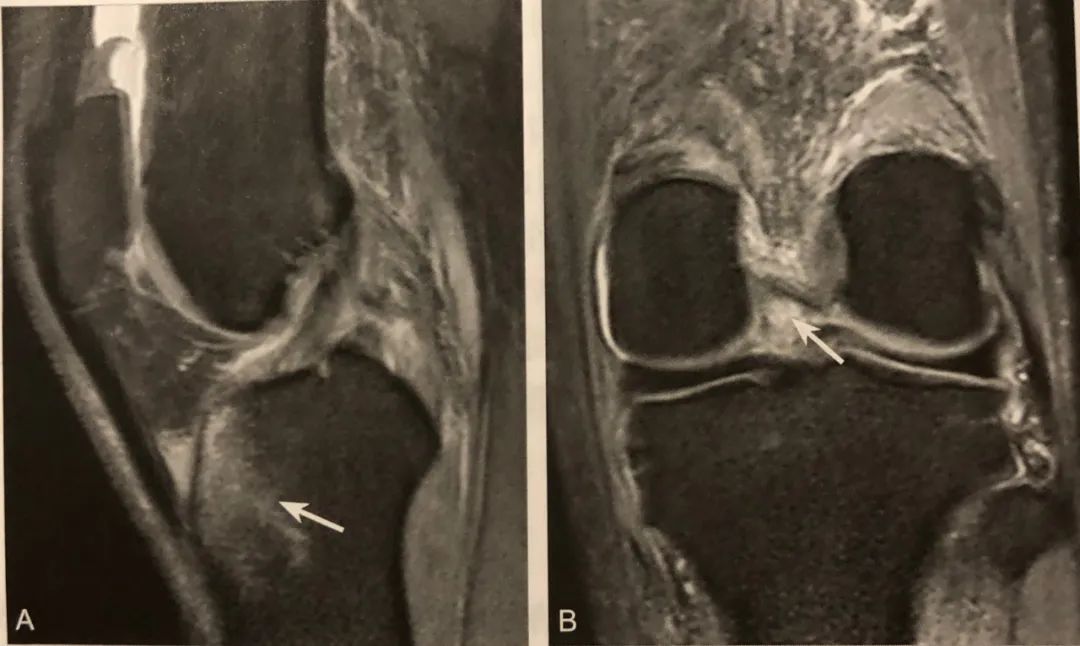

1. 半月板移位的直接征象;

2. 在膝关节 MRI 冠状位半月板体部的中央平面观察;

3. 半月板外缘超过胫骨平台关节面边缘 ≥3mm ;

4. 常伴半月板复杂撕裂或膝关节支持系统损伤,应注意观察。